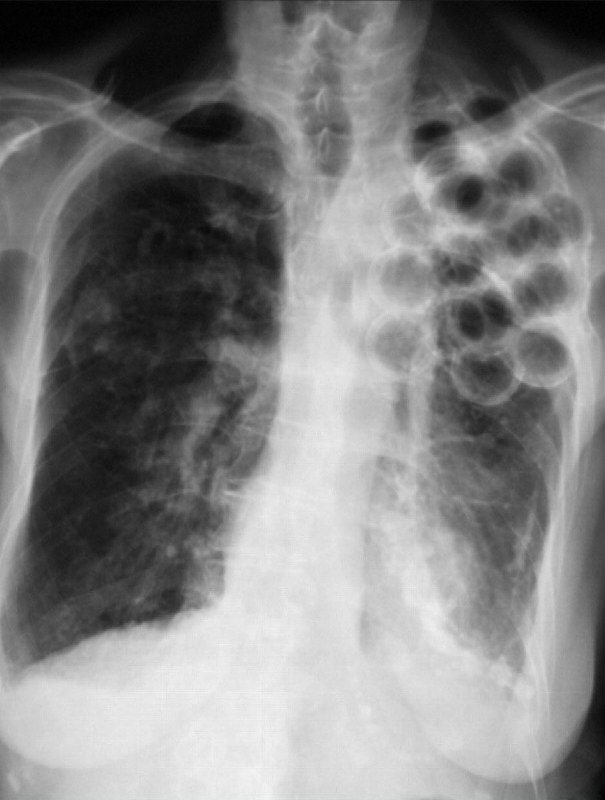

Here’s an absolutely wild Chest X-Ray you won’t see every day

What’s the diagnosis?